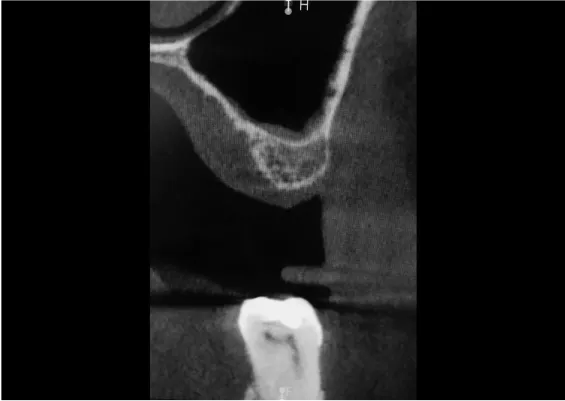

Odbudowa kostna w ODCINKACH BOCZNYCH SZCZĘK - PODNIESIENIE DNA ZATOKI SZCZĘKOWEJ (SINUS LIFT)

Technika odbudowy kostnej stosowana w celu wszczepienia implantów w zanikłe, boczne odcinki szczęk. Najistotniejszą przyczyną utraty kości wyrostka zębodołowego szczęk w odcinkach bocznych są ekstrakcje zębów. Niedostatek kości w wymiarze pionowym stanowi szczególną anatomiczną przeszkodę dla implantacji w okolicy dna zatoki szczękowej. Chcąc odbudować uzębienie i przywrócić funkcję żucia, trzeba podjąć wieloetapowe leczenie rekonstrukcyjne.

Zabiegiem, który rozwiązuje ten problem, jestpodniesienie dna zatoki szczękowej (sinus lift), czyli odbudowa kostna w okolicy zębów trzonowych. Ubytek kości uzupełniany jest materiałem kościotwórczym, który układany jest pod błoną wyścielającą zatokę szczękową, zwaną membraną Schneidera. Zmniejszając objętość zatoki szczękowej, tworzy się tym samym stabilną strukturę kostną, umożliwiającą zabieg implantacji wszczepów śródkostnych.